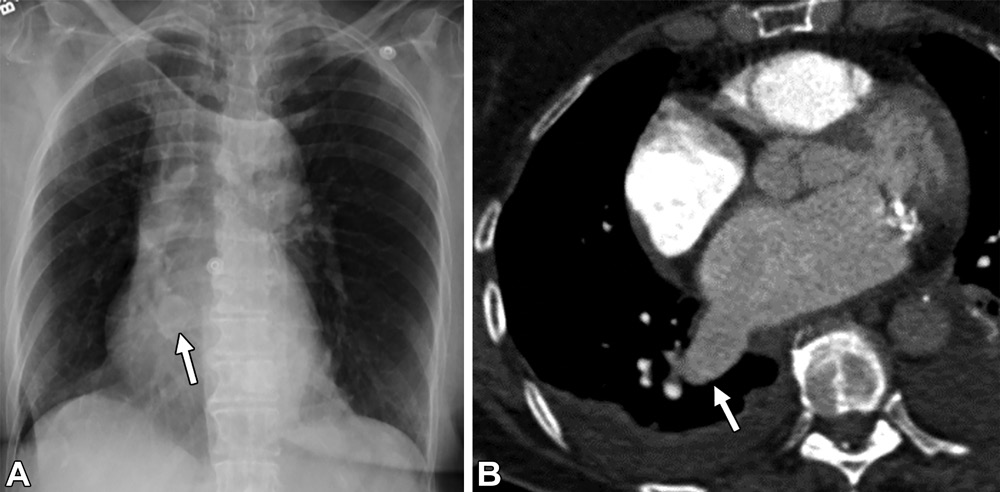

PAVM。轴位CT图,32岁男性,遗传性出血性毛细血管扩张症,因右向左分流导致的慢性低氧血症。(A,B)轴位CT图,可见右肺下叶PAVM的病灶(白色信号)及引流静脉(白色箭头)。(C,D)轴位CT图,可见供血动脉大于3mm(白色箭头)。(E)右肺下叶另见一个PAVM,在供血动脉及引流静脉之间的磨玻璃密度影(白色圆圈),提示显微镜下毛细血管扩张。(F,G)一个复杂的PAVM位于左肺下叶,可见三个供血动脉(F图中白色虚线箭头)以及一个粗大的引流静脉(白色星号),注意观察引流静脉比供血动脉大。

肺静脉曲张。54岁男性,胸片异常。(A)前后位胸片可见右肺下叶异常扩张的血管结构(白色箭头)。(B)轴位CT增强图,可见右肺下叶肺静脉曲张。